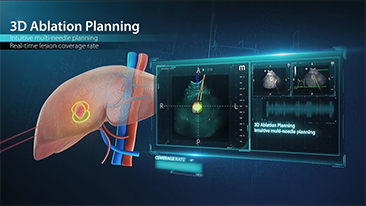

Solusi Pencitraan Umum Resona dari Mindray membantu para dokter mewujudkan diagnosis dan hasil pengobatan yang lebih akurat dan efisien melalui pemerik aplikasi subdivisi yang komprehensif dan alat bantu aplikasi klinis yang efisien.